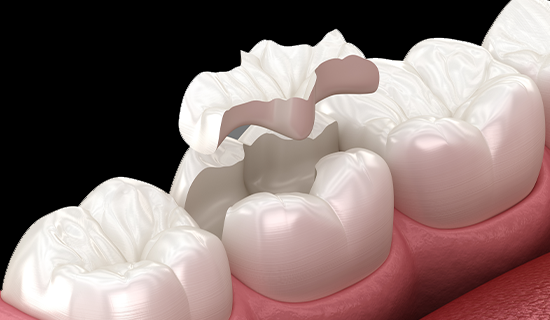

2) 인레이/온레이 (Inlay/onlay)

충치 부위를 떼우는 방식이 아니라, 치아의 손상된 부분에 맞춰 제작한 보철물을 끼워 접착하는 치료 방법입니다. 주로 충치가 크거나 깊을 때 사용됩니다. 주로 세라믹을 재료로 하나 때에따라 강도가 좋은 금을 사용하기도 합니다.장점

· 저작력이 큰 어금니에도 적합합니다.

· 정밀하게 맞아 떨어져 수명이 깁니다.

· 재료에 따라 심미성이 우수합니다.

(세라믹, 금 등)

단점

· 최소 2번의 내원이 요구됩니다.

· 큰 충치나 어금니(사이충치)에는 적합하지 않을 수 있습니다.